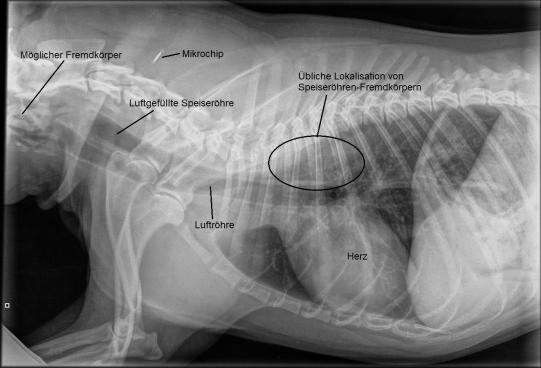

Der sonst fröhliche junge Rüde scheint deprimiert und schluckt fortwährend leer, mehrfach würgt er auch eine grosse Menge weissen Schaums hervor. Ansonsten ist der Untersuch unauffällig. Gegenstände, welche zu gross zum normalen Abschlucken sind, bleiben in der Speiseröhre meist im Brustkorb auf Höhe des Herzens stecken. Erstaunt stellen wir auf einem Röntgen aber fest, dass sich an dieser Stelle kein Fremdmaterial befindet. Hingegen scheint die im Röntgen ganz am Rande erkennbare Rachenregion verdächtig.